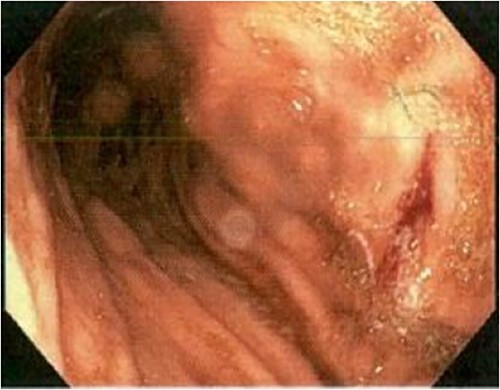

An 85-year-old female presented to hospital with melena and anaemia. She was functionally independent. Her past medical history included hypertension, and medications included irbesartan and low dose aspirin for primary cardiovascular prevention. She was haemodynamically stable with a haemoglobin of 75 g/L (previously normal) and urea of 21.9 mmol/L. CT-angiogram (CT-A) demonstrated no active contrast extravasation. She received two units of packed red blood cells (PRBCs), was commenced on intravenous pantoprazole, and underwent gastroscopy. This revealed a linear ulcer on the greater curvature of the stomach 5 cm from the gastroesophageal junction (GOJ) with an adherent clot and no active bleeding (Figs 1 and 2). The ulcer was injected with adrenaline and haemostasis achieved. The first and second part of the duodenum (D1, D2 respectively) appeared normal.

Initial gastroscopy - linear gastric ulcer on greater curvature of stomach.